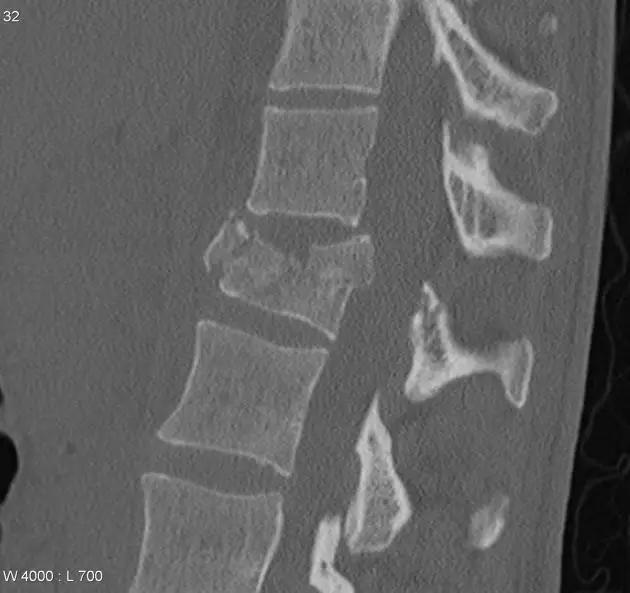

脊柱骨折

1. Burst 骨折

椎体轴向压力造成的骨折,通常发生骨折碎片向外侧的移位。可以发生在颈椎、胸椎或腰椎。

(来源:Radiopaedia)

3. Chance 骨折

胸腰段椎体的分离性骨折,伴随脊髓、神经根、椎体的水平方向的崩裂骨折。又称座带骨折(seatbelt fracture)。

由 Chance 于 1948 年首先描述此骨折,故文献又常称 Chance 骨折,为一种屈曲拉伸骨折。典型的损伤机制为汽车座带束于患者腰腹部,当高速行驶的汽车突然减速或撞车时,座带支点以上的躯干屈曲,前冲力还同时产生一个向前拉伸的力量。将椎体由后方向前撕裂,骨折线横过椎体、椎弓根和椎板,椎体后部的韧带完全撕裂。有时前纵韧带亦可撕裂,常合并有神经系统的症状。